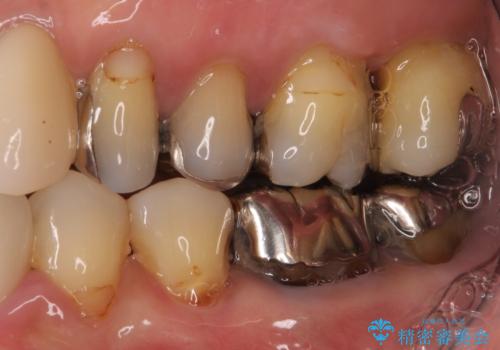

- 歯を磨く度に奥歯から出血するとのことで来院された患者様です。

歯周ポケット検査を行ったところ、6-8mmの歯周ポケットが散見され(正常では3mm以下)、歯周病治療が必要と判断されました。

仮歯に置き替え、歯周外科処置(APF、歯肉弁根尖側移動術)による歯周ポケット除去を行った後に、オールセラミッククラウンにて補綴することとしました。